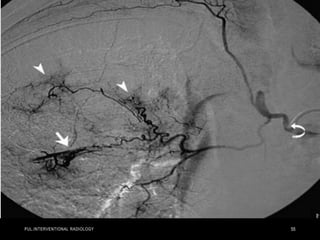

• Pulmonary angiography in a 57-year-old woman in shock from

acute bilateral massive PE. Initial right (a) and left

(b) pulmonary angiograms show near-complete obstruction.

Pulmonary artery pressure was 73/18 mm Hg. Final right (c) and

left

(d) images after suction thrombectomy and catheter-directed

thrombolytic agent injection into each main descending

pulmonary

artery. Pulmonary artery pressure was reduced to 36/16 mm Hg.

(Images courtesy of Daniel Y. Sze.)